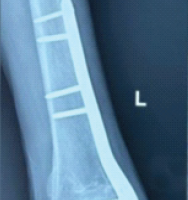

A 52-year-old patient presented with pain in the left shoulder. X-ray showed a lytic lesion on the humerus, and PTH was on the higher side, so a diagnosis of HPT was made. The patient was not willing to undergo a parathyroidectomy, and nailing was done, but intraoperatively, we were not able to lock the distal screw due to the fragility of the bone, so we put a U slab. A parathyroidectomy was done, and the bone healed within 2 months with a full range of motion.